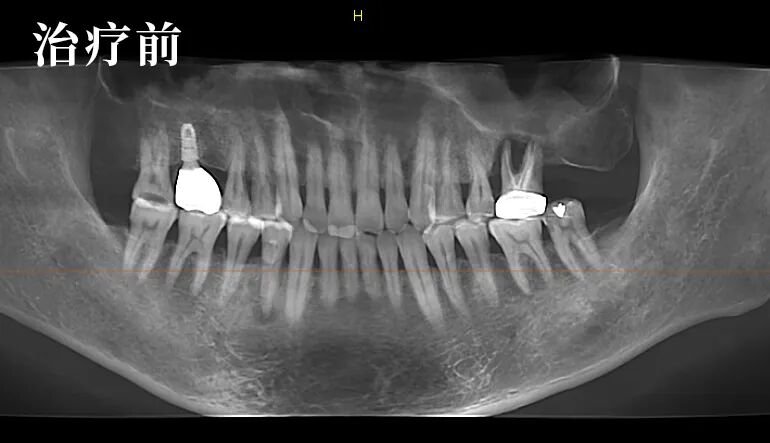

经过详细的检查及影像对比,朱医生发现了问题的特殊性:局部的炎症并非疼痛的主因,真正的问题在于患者自身双侧关节的先天不对称,导致了咬合力的异常分布。

这是一个典型的“继发性问题”——原有的修复体与患者独特的生理结构之间,产生了需要精细调整的力学冲突。

他邀请李先生一同观看影像,耐心解释道:“您看,问题的核心在于关节的先天条件导致了力量失衡。我们的目标不是简单地为你消炎,而是为您重建一个专属的、稳定的咬合平衡。”